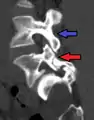

Degenerative spondylolisthesis at L5 - S1.

(A) CT sagittal view of a low grade slip.

(B) Lateral radiograph pre-operative intervention.

(C) Surgically treated with L5 – S1 decompression, instrumented fusion and placement of an interbody graft between L5 and S1.